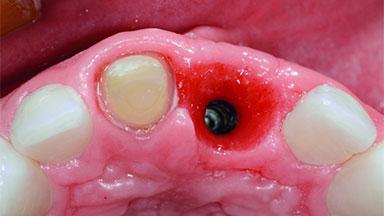

Replacement of an Ankylosed Upper Left Central Incisor: Bone Augmentation and Socket Grafting, Late Placement of an RC Bone Level Implant

A 15-year-old male patient was referred to us by his pediatric dentist in June 2004 for evaluation of treatment options for his failing tooth 21. The patient had recently seen an endodontist for internal bleaching and been advised that there had been significant resorption and ankylosis. The patient’s mother was concerned because the tooth appeared shorter than the adjacent one. His past dental history was significant for trauma (September 2001), where the tooth had been avulsed and reimplanted. Teeth 11 and 21 had been endodontically treated.